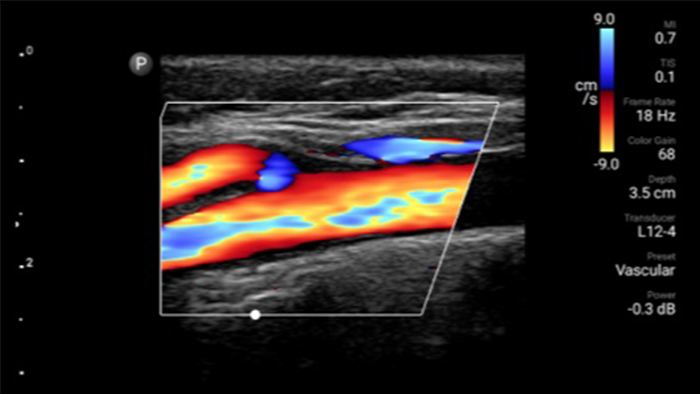

Transductor de matriz lineal de banda ancha Lumify L12-4

Reduzca las complicaciones en procedimientos guiados por aguja

El ultrasonido portátil Lumify para anestesiología le ayuda a visualizar claramente la definición de los bordes con la colocación de la aguja, los nervios circundantes, los vasos sanguíneos y los planos fasciales.